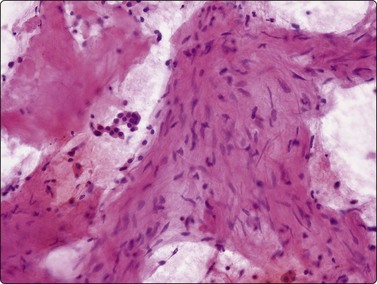

image image

Fig. 8.13 Anthraco-silicosis; progressive massive fibrosis

Bilateral upper zone/hilar lung masses in a miner. Dense masses of macrophages and fibrous tissue (A, H&E, MP; B, H&E, HP).

Birefringent silica and collagenous tissue (Fig. 8.13) or asbestos bodies may help confirm silicosis or exposure to asbestos.203 However, concomitant malignancy, tuberculosis or other infections may be the cause of the localized opacity in these patients.204